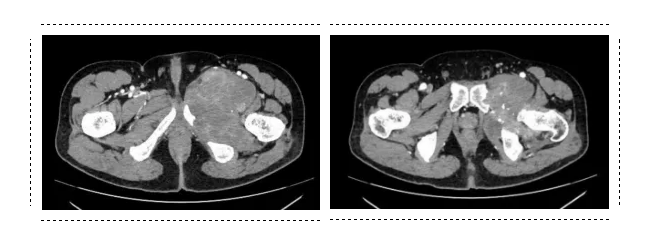

经肉瘤MDT团队的讨论,决定先采取科室特色大剂量化疗联合抗血管生成治疗对患者进行术前的新辅助治疗。经过3周期的化疗后,影像学评估患者的肿瘤部分缩小。专家团队一致认为手术时机成熟。

杨吉龙主任团队利用三维数字化重建及3D建模技术首先建立了肿瘤的3D模型,并利用3D模型进行了计算机模拟的肿瘤切除,确定了安全的手术边界,并精准定制用于重建的半骨盆及髋关节。